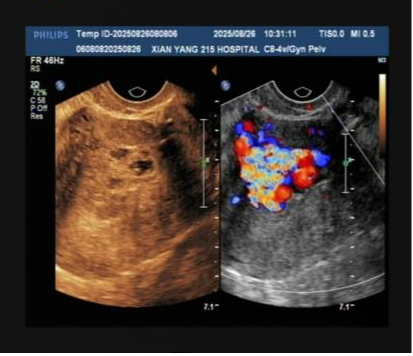

術(shù)前檢查影像

檢查結(jié)果很快傳來,B超結(jié)果顯示宮腔內(nèi)殘留組織伴豐富血流,高度懷疑“子宮動(dòng)靜脈瘺”;隨后的MRI檢查進(jìn)一步證實(shí),患者宮腔內(nèi)不僅有異常病灶,鄰近子宮前壁還出現(xiàn)多發(fā)流空信號——這意味著子宮動(dòng)脈與靜脈之間形成了異常通道,動(dòng)脈血直接涌入靜脈,一旦通道破裂,就可能引發(fā)難以控制的致命性大出血。